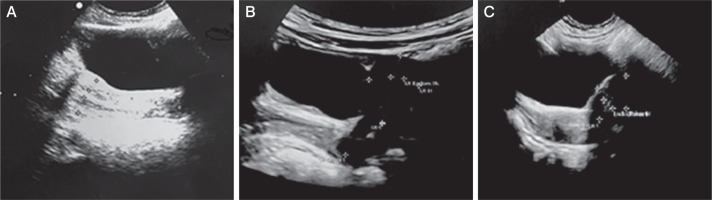

Figure 3

Pelvic ultrasound performed during mitotane treatment presents signs of precocious puberty. A) Case 2: anteverted uterus with an anteroposterior (AP) diameter of 15 mm, and a length of 26 mm. The endometrial thickness is 3.5 mm, and the cervical length 23 mm. B) Case 3: anteverted uterus with AP dimensions of 13 mm, length of 24 mm, cervix length of 21 mm, and endometrial thickness of 4 mm. C) Case 4: anteverted uterus with AP diameter 14 mm, length 20 mm, and endometrial thickness 4.8 mm

After more than 9 months of mitotane treatment, the 3.5-year-old girl was readmitted to the Endocrinology Department due to vaginal bleeding. Tanner’s stage was assessed as P1, B2. A GnRH test was performed, and the result was prepubertal. The oestradiol concentration was within the normal range. Pelvic ultrasonography showed an anteverted uterus with an anteroposterior (AP) diameter of 15 mm and a length of 26 mm. The endometrium measured 3.5 mm, and the cervical length was 23 mm. The right ovary measured 18 × 10 × 17 mm with a volume of 1.7 ml (no larger follicles were observed) (Figure 3A). The left ovary could not be visualized.

Additionally, asymmetrical development of breast tissue was noted. A recurrent episode of vaginal bleeding occurred one month after hospitalization, which lasted 3 days. Total body MRI did not reveal any signs of tumour regrowth but described an enlarged uterus with an endometrial thickness of 4 mm. Due to mitotane treatment complications and neoplastic disease remission, it was decided that mitotane would be discontinued after 12 months. After mitotane cessation, there was no progression of maturation.

At 16 months of age (4 months after starting mitotane treatment), the girl was readmitted to the Department of Endocrinology due to breast gland development and reoccurrence of pubic hair growth observed for the past 2 weeks. Regression of development was also noted; she stopped walking and spoke less. She experienced limb tremors and had an unsteady gait. Furthermore, the parents reported daytime sleepiness, night terrors, anxiety, decreased appetite, and weight loss. The puberty stage was assessed as P2 (sparse hair), B2. Labial hypertrophy, hyperpigmentation in the posterior labial commissure, and hyperpigmentation of the nipple-areolar complex were noticed. Laboratory tests revealed a decreased serum sodium level (133 mmol/l) with a potassium level of 5.36 mmol/l and an ACTH level of 671 pg/ml, and an undetectable cortisol level before administration of the next dose of HC. The HC dose was increased to 15 mg/day (27.3 mg/m2). Based on the evaluation of thyroid function, hypothyroidism was diagnosed (TSH 6.5 uIU/ml (N: 0.87–6.15 uIU/ml), fT4 0.77 ng/dl (N: 0.94–1.44 ng/dl), fT3 3.63 pg/ml (N: 3.3–5.2 pg/ml), and anti-thyroid antibodies were negative. The patient required treatment with levothyroxine at a dose of 1.13 µg/kg/day. Pelvic ultrasound revealed the following: uterine body length 20 mm, anterior-posterior diameter 14 mm, endometrial thickness 4.8 mm, right ovary volume 2.4 ml, left ovary volume 3.7 ml, and multiple follicles in the ovaries (Figure 3C). A GnRH test resulted in prepubertal findings with an oestradiol concentration of 21.30 pg/ml (N < 11.8–62.7). Bone age was assessed as 1 year and 6 months (consistent with chronological age). The controlled mitotane level was 21.4 µg/ml. Neurological examination revealed features of cerebellar ataxia. After 4 months of mitotane treatment, due to the increased severity of side effects associated with mitotane, including PP and neurological disturbances, the decision was made to discontinue the mitotane administration. Neurological symptoms have largely regressed about a month after mitotane cessation; there are only limb tremors, and only with precise movements. The follow-up period is 9 months with no features of recurrence.